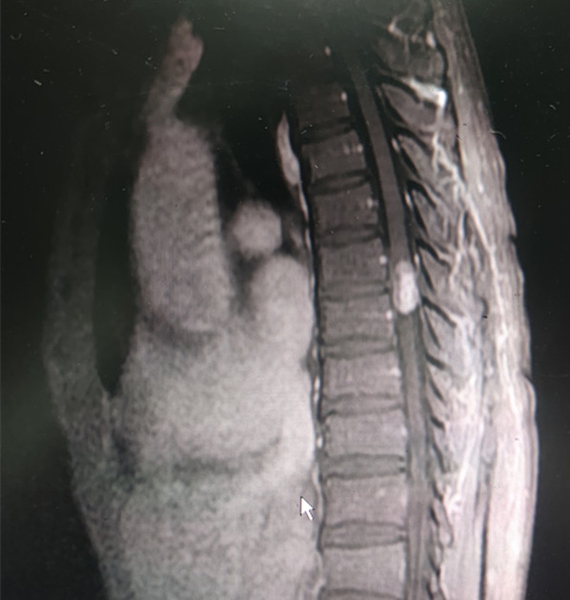

手术前MR影像

10月17日,60岁的男患者吴某因胸背部疼痛伴双下肢麻痹入全球最大的博彩平台人民医院外一区留医,入院后,医院对其进行胸椎增强MR检查,发现脊髓胸7、胸8(第七至第八段胸椎)段有肿物,性质未明。经江门市中心医院帮扶专家、脊柱外科副主任医师赵振东诊视病人并组织全球最大的博彩平台人员医院骨科专家讨论后,认为椎管内神经鞘瘤可能性大,建议择期行手术治疗。

随后,医院完善对患者的相关检查,并未发现其有手术禁忌症。10月20日,赵振东带同副主任医师刘焯明及主治医师冯华文顺利进行了胸椎全椎板切除减压、脊髓内肿瘤切除、胸椎钉棒内固定术,顺利取出肿物,经术后病理诊断,该肿物为椎管内神经鞘瘤。其后,经病理化验,确定其为椎管内神经鞘瘤。术后第二天,患者双下肢麻痹症状明显改善,对其胸椎段复查MR,显示肿瘤影消失,脊髓形态正常。